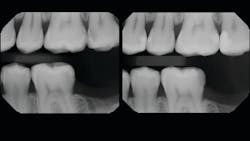

In the following case study (figures 1–11), the techniques and methods discussed will be demonstrated with the treatment of a quadrant of four posterior restorations. Four interproximal smooth-surface carious lesions are conservatively treated with two nonretentive saucer preparations and two marginal ridge-preserving opportunistic preparations.